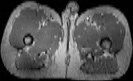

Visible Human male: Sectio transversalis 1958

NMR

Pd                          / T2 \                         T1